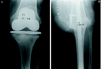

Se presentaron complicaciones postoperatorias en doce pacientes, de las cuales las más notables fueron alteraciones de la cicatrización en cinco casos, infección de la herida quirúrgica en tres y en otro hubo una parálisis del nervio ciático poplíteo externo. La consolidación se define como una fusión sólida clínicamente, con evidencia radiográfica de trabeculación ósea a través del foco de artrodesis. Se produjeron tres roturas de clavos, en uno de ellos se aplicó una ortesis y en los dos restantes se practicó un nuevo enclavado con aporte de injerto. En los tres casos se ha obtenido la consolidación a los siete meses, como promedio (Fig. 4).

Figura 4. Aflojamiento protésico. A: Radiografía preoperatoria. B: Rotura de clavo 18 meses después de la cirugía. C: Nuevo enclavado.